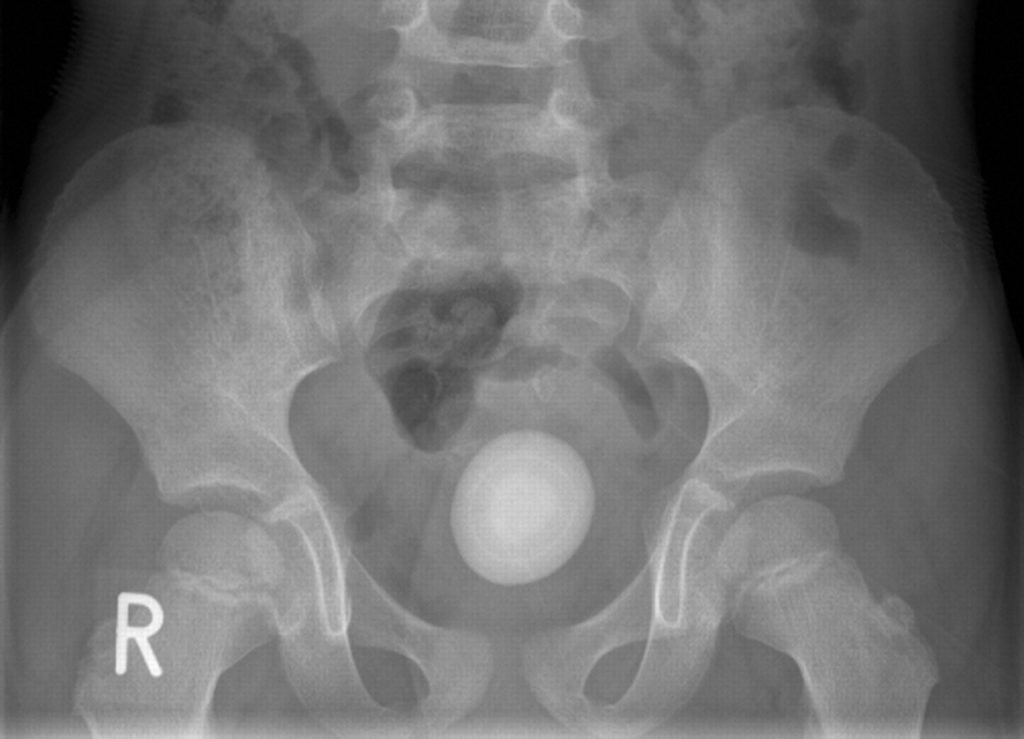

Sỏi bàng quang (vesical hay cystolith) thường có dạng hình tròn, hiếm khi xù xì góc cạnh. Sỏi bàng quang có nguồn gốc khá đa dạng, có thể rơi từ đường tiểu trên xuống như sỏi thận, sỏi niệu quản,…

- Chụp X – quang và CT-scan giúp xác định vị trí chính xác của sỏi bàng quan từ đó giúp cho việc điều trị dễ dàng hơn. .